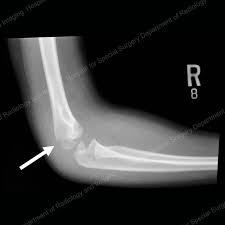

Elbow Fractures In Children An Overview Hss Edu

Elbow Fractures In Children An Overview Hss Edu from www.hss.edu